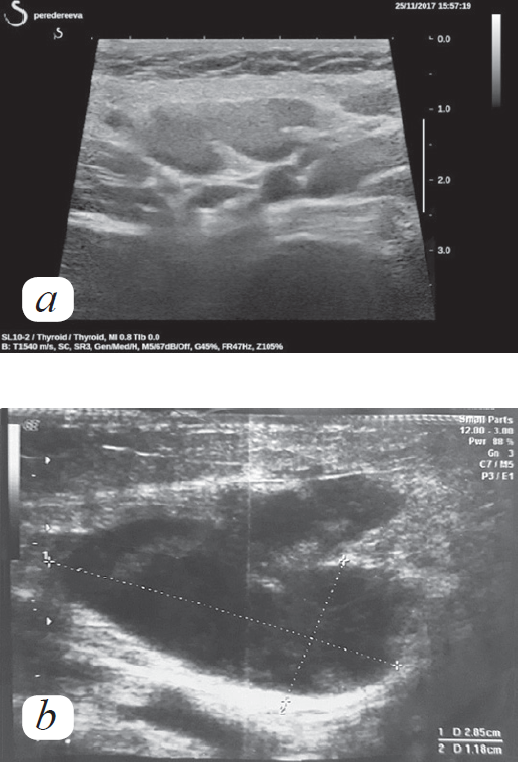

Болезнь Кавасаки — это острое лихорадочное заболевание детского возраста, одним из характерных проявлений которого является лимфаденопатия. Чаще всего поражение лимфатических узлов представлено односторонним болезненным увеличением одного или нескольких лимфоузлов шейной группы не менее 1,5 см в диаметре, появляющимся одновременно с лихорадкой и постепенно исчезающим после купирования воспаления. Возможно также менее значительное увеличение лимфоузлов других локализаций: подмышечных, паховых, паратрахеальных, парааортальных, ретроперитонеальных, лимфатических узлов брыжейки. Морфологически наиболее типичны негнойное некротическое поражение лимфоузлов с наличием субкапсулярных некротических очагов, а также неспецифические изменения в виде увеличения паракортикальной зоны и расширения синуса. В статье представлен клинический случай диагностики болезни Кавасаки, сопровождающийся выраженной лимфаденопатией, сохранением лихорадки и прогрессированием лимфаденопатии, появлением надключичного лимфоузла после введения внутривенного иммуноглобулина, что свидетельствовало о негладком течении заболевания и потребовало проведения дифференциальной диагностики, в первую очередь с лимфопролиферативным заболеванием. Представлен обзор «необычных» случаев лимфаденопатии у пациентов с болезнью Кавасаки, описанных в литературе. Подчеркнута важность проведения гистологического исследования лимфатического узла при негладком течении заболевания. Описаны гистологические варианты поражения лимфатических узлов у пациентов с болезнью Кавасаки.